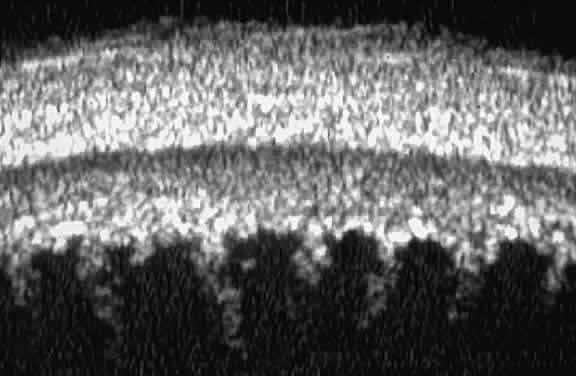

certain patients with open-angle glaucoma, UBM can provide

information that may be of some diagnostic value (Fig. 10). For example, in pigment dispersion syndrome (see Fig. 10A),6 UBM typically reveals posterior bowing of the peripheral iris (“q” configuration

of peripheral iris by Spaeth classification5). In plateau iris syndrome (see Fig. 10B),7 UBM usually reveals abnormally steep anterior angulation of the peripheral

iris (“s”configuration of peripheral iris by Spaeth classification5), insertion of the iris from the anterior ciliary body, and retroiridic

projection of the ciliary processes. In eyes with peripheral anterior

Fig. 10. UBM features of special glaucoma cases. A. Pigment dispersion syndrome with posterior bowing of peripheral iris (“q” configuration by Spaeth gonioscopic grading system). B. Plateau iris syndrome with origin of iris from anterior surface of ciliary

processes behind peripheral iris, slitlike narrowing of peripheral

angle, and abrupt transition from steep peripheral iris to flat iris

midzone. C. Broad peripheral anterior synechia with posterior bowing of nonadherent

iris. D. Peripheral anterior synechia with aqueous-filled slit between site of

iridocorneal adhesion and iris root after cataract extraction with implantation

of posterior-chamber IOL. Fig. 10. UBM features of special glaucoma cases. A. Pigment dispersion syndrome with posterior bowing of peripheral iris (“q” configuration by Spaeth gonioscopic grading system). B. Plateau iris syndrome with origin of iris from anterior surface of ciliary

processes behind peripheral iris, slitlike narrowing of peripheral

angle, and abrupt transition from steep peripheral iris to flat iris

midzone. C. Broad peripheral anterior synechia with posterior bowing of nonadherent

iris. D. Peripheral anterior synechia with aqueous-filled slit between site of

iridocorneal adhesion and iris root after cataract extraction with implantation

of posterior-chamber IOL.